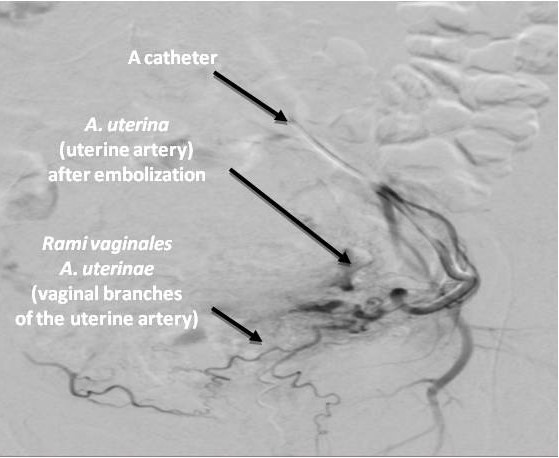

In the endovascular intervention in UL, special attention is paid to the segment of the uterine artery that ascends towards the uterine-tubal angle and gives off numerous tortuous branches directly to the uterine body and cervix (the zone of direct branching of the uterine artery into the terminal branches) (Figure 2).

Fig. 2. A selective angiogram of the left uterine artery of a female patient Z., 40 years, after embolization with preservation of the isthmic and vaginal branches.